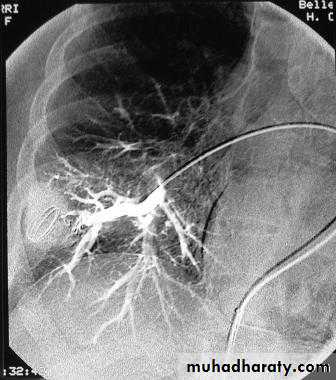

Angiography of coronary vessels